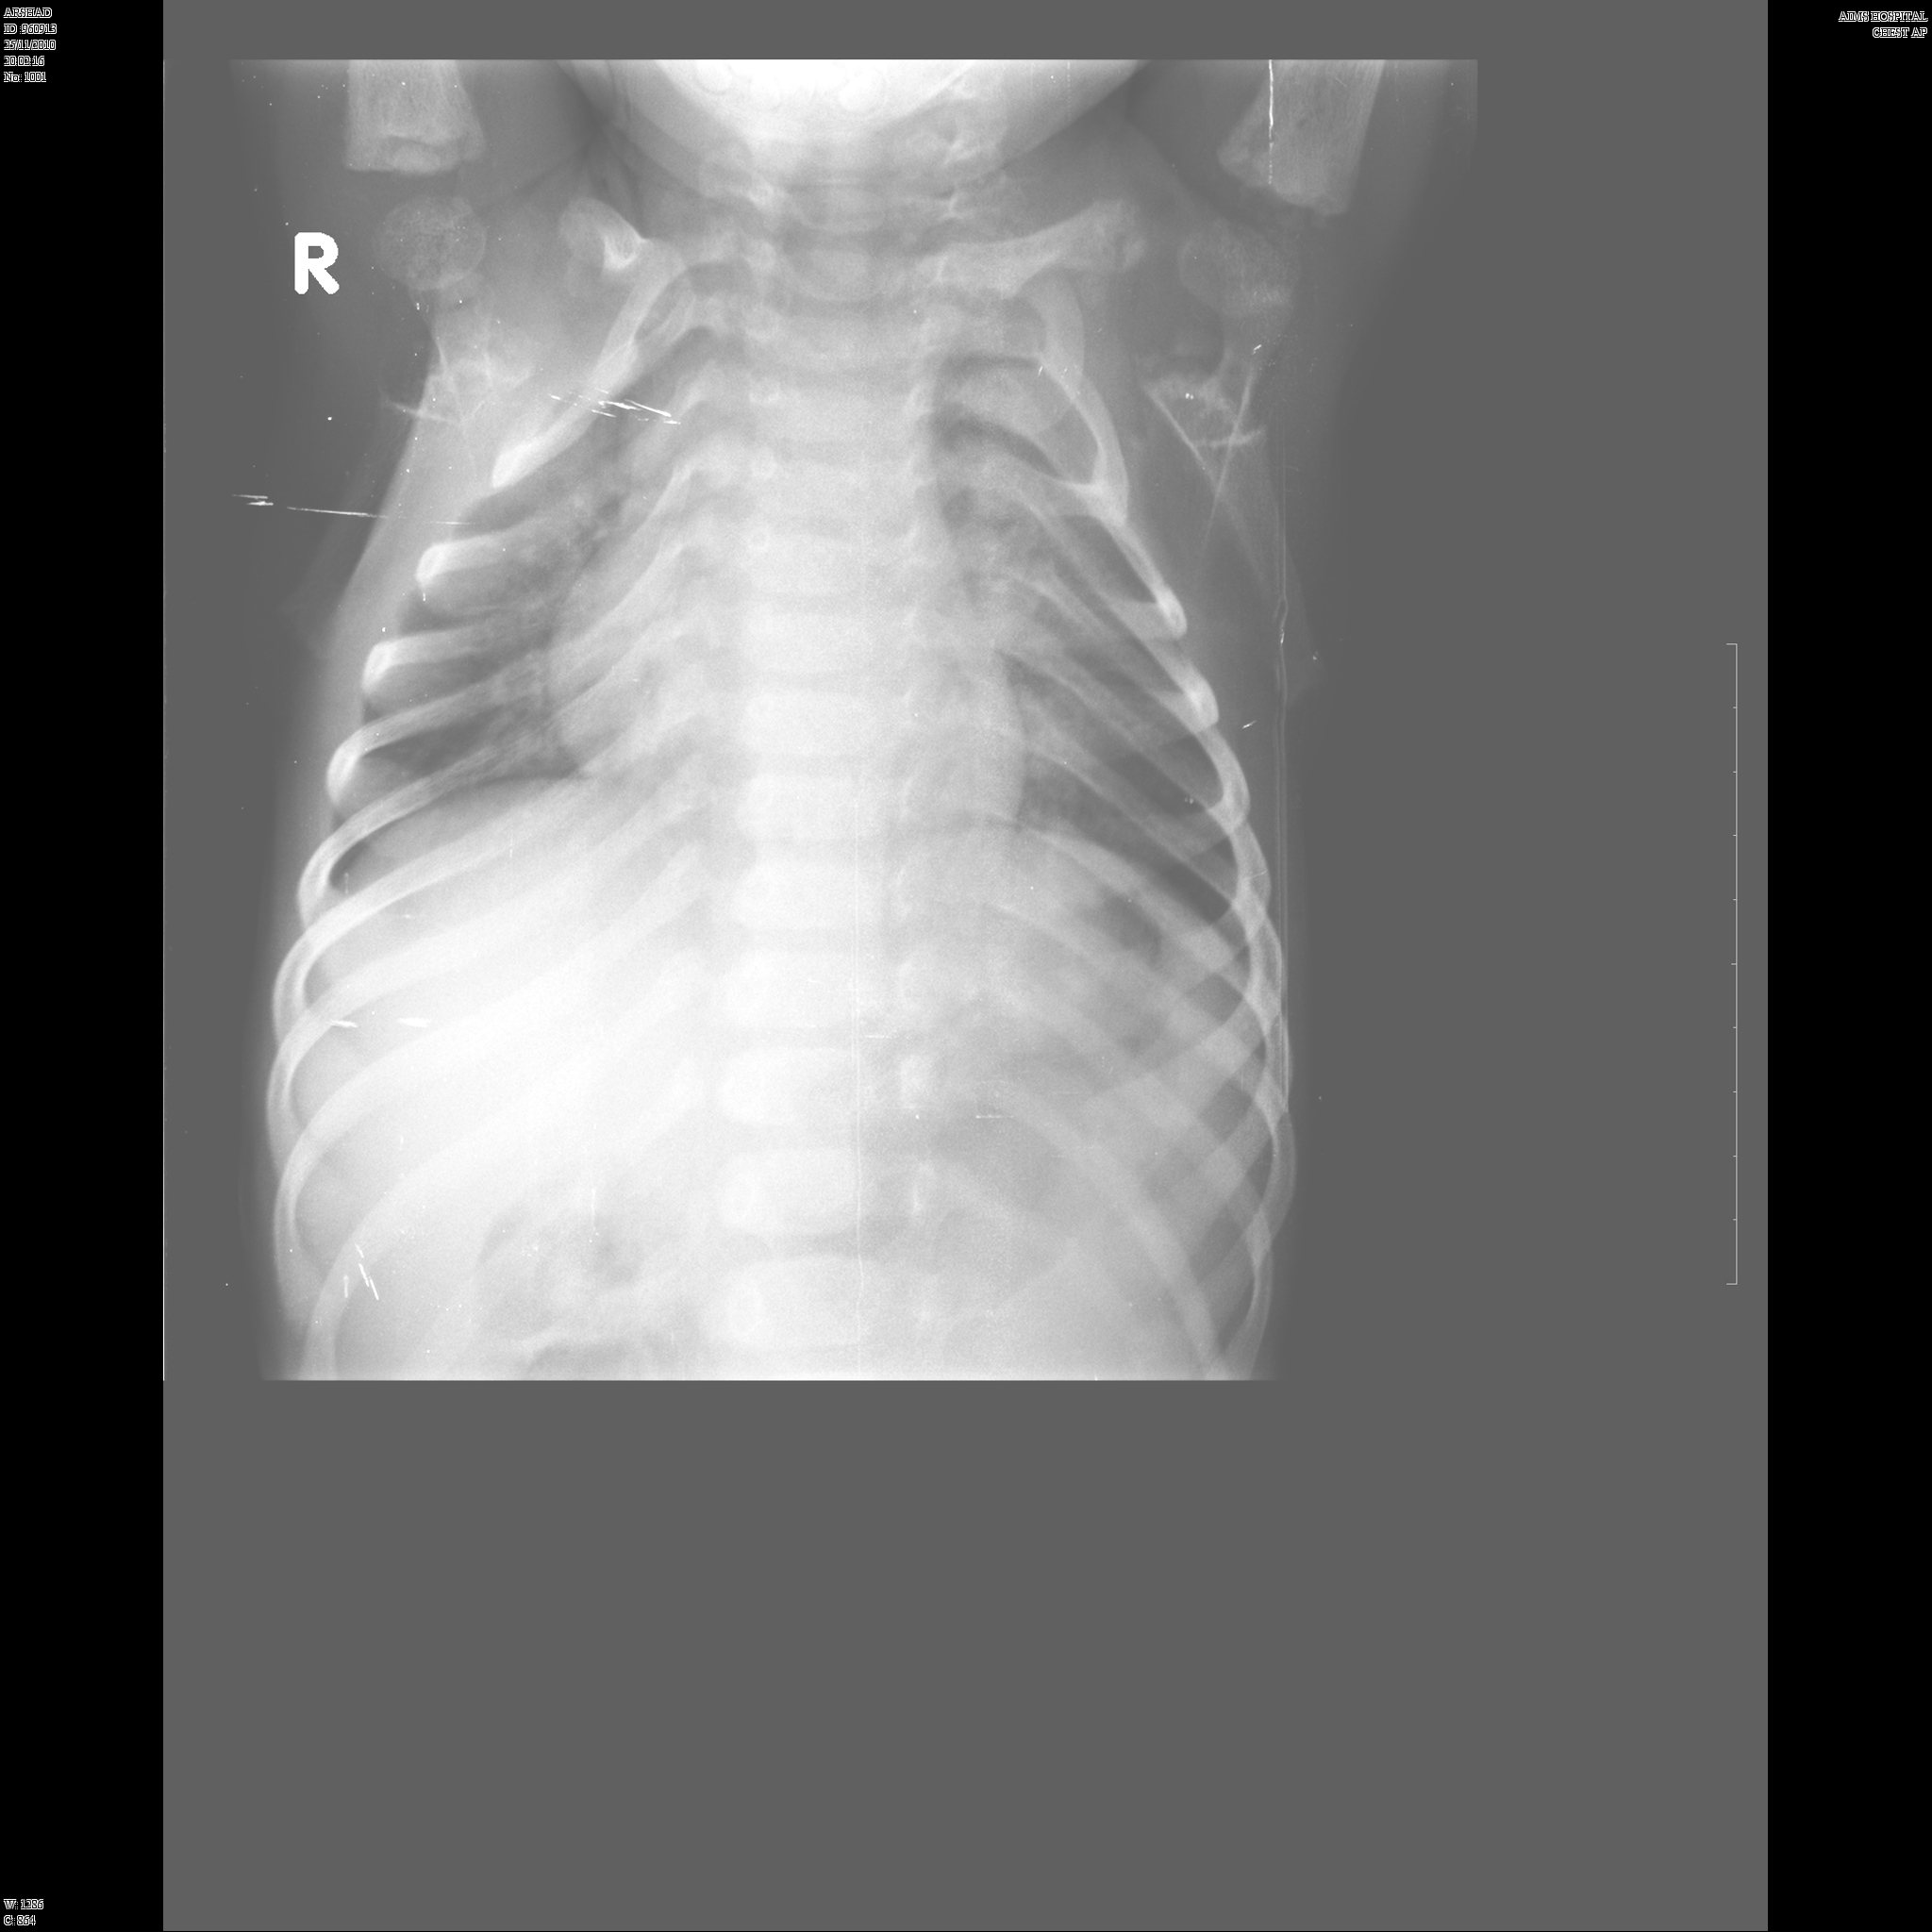

Here we share radiographic images to help with diagnosis of Jansen's disease:

Jansen's patients show extreme disorganization of the metaphyses of the long bones and of the metacarpal and metatarsal bones in sharp contrast to the almost normal appearance of the epiphyseal centers, which on x-ray appear widely separated from the long bones. The chin is receding. The fingers, especially the distal phalanges, are very short. The spine, pelvis, and lower legs are distorted.

Jansen's patients present at birth with prominent eyes, choanal stenosis, wide cranial sutures, highly arched palate, micrognathia, rib fractures, and irregularities of the metaphyses of the long bones resembling rickets. At the age of 2-3, patients show stunted growth, waddling gait, enlarged joints, prominent supraorbital ridges, and frontonasal hyperplasia.